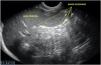

Se realizó ecografía abdominal donde se objetivó hepatomegalia con hipoecogenicidad periportal en porta principal y sus ramas (figs. 1 y 2), y discreta esplenomegalia con múltiples bazos accesorios subcentimétricos en hilio (fig. 3). Se remitió al centro hospitalario de referencia con la sospecha de síndrome mieloproliferativo, donde fue diagnosticado de leucemia mieloide aguda.

Corte longitudinal-oblicuo del hipocondrio izquierdo, obtenido mediante sonda convex a nivel de epigastrio, en el que se visualizan: a) Parénquima hepático a nivel del lóbulo izquierdo (LHI) con secciones transversales de manguitos periportales hipoecogénicos de mayor (M) y menor tamaño (m); b) Ampliación de la imagen previa con cuantificación del diámetro de uno de manguitos periportales. Estómago (E).